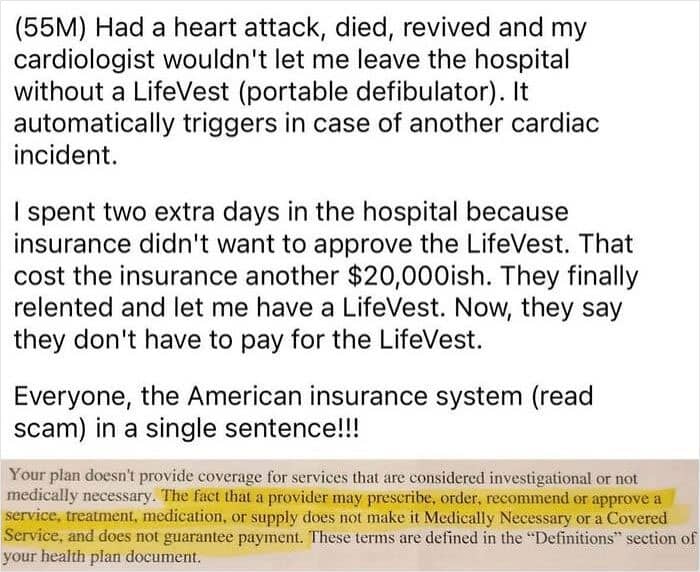

#52 American Insurance

#53 Noticed A New Sign On Display At My Last Doctor’s Appointment. Why Even Have Insurance?

#54 Price Of My Chemo Pills Every Month After Insurance And A Savings Card